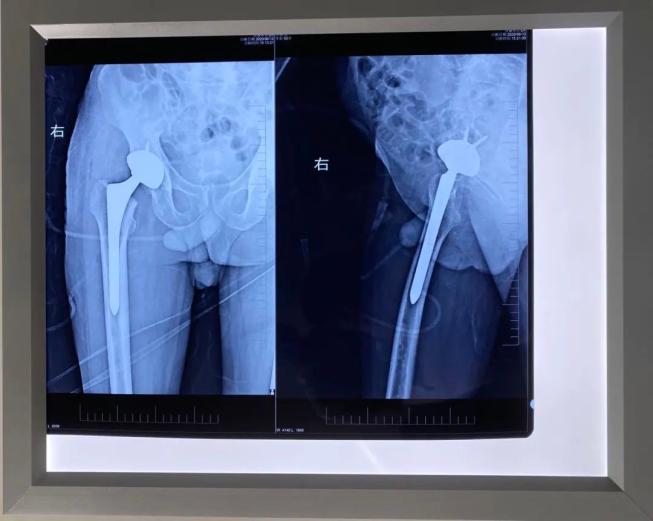

2020年06月10日,我院外科成功为一位53岁贫困户大叔实施右侧人工全髋关节置换术。受尽病魔困扰的大叔终于摆脱轮椅能站立行走,近日即将出院。

今年6月,在驻村扶贫工作队人员指引下,来到我院外科就诊,外科主任胡柱主治医师仔细评估患者病情及经济情况后予收治入院。经过术前准备、术后护理及存在的风险情况的充分评估,制定了最佳的手术治疗方案,在来宾市人民医院专家的协助下,成功地为患者施行了右侧人工全髋关节置换术。

术后患者恢复良好,已能借助助行器下床行走和康复训练,基本解决了生活不能自理问题,缓解了长期需要人照顾的家庭压力。

在医疗费用上按政府健康扶贫兜底政策给予了最大程度照顾。经主治医师韦正果医师介绍:根据病情评估,预计三个月后再行左侧人工全髋关节置换术,此后患者就可真正摆脱生活不能自理、长期需要人照顾的困境。